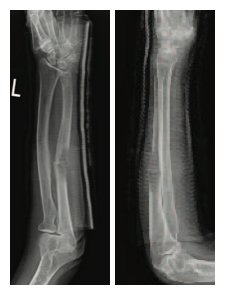

Diagnosis: Metastatic Renal Cell Carcinoma with pathologic fracture of the right radius and left ulna and significantly compromized bone quality.

Description of fracture: Pathologic fracture at the radial shaft with bony destruction measuring 5.8 cm; pathologic fracture mid-ulna measuring

5.2 cm with soft tissue component

Left Ulna

Pre-op